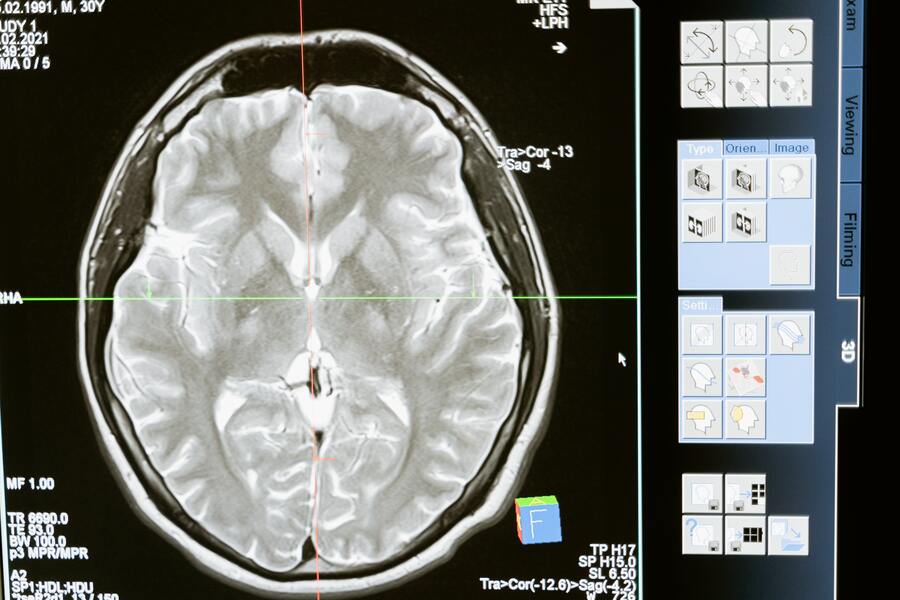

《CNN》報導,類澱粉蛋白在器官中不正常的堆積,會造成功能退化或障礙,如阿茲海默症、帕金森氏症中,都可以觀察到神經系統中有大量類澱粉蛋白沉澱。對此,兩種藥物都能有效清除大腦中的不良物質,減緩病症惡化的速度。

然而,有三分之一接受實驗的患者出現了腦腫脹的副作用,嚴重甚至有危及生命的可能性。對此,布里斯托爾大學博士寇斯德表示,雖然該藥物存在著「明顯副作用」且「缺乏長期研究數據」,但它確實能夠幫助阿茲海默症患者活得更久。